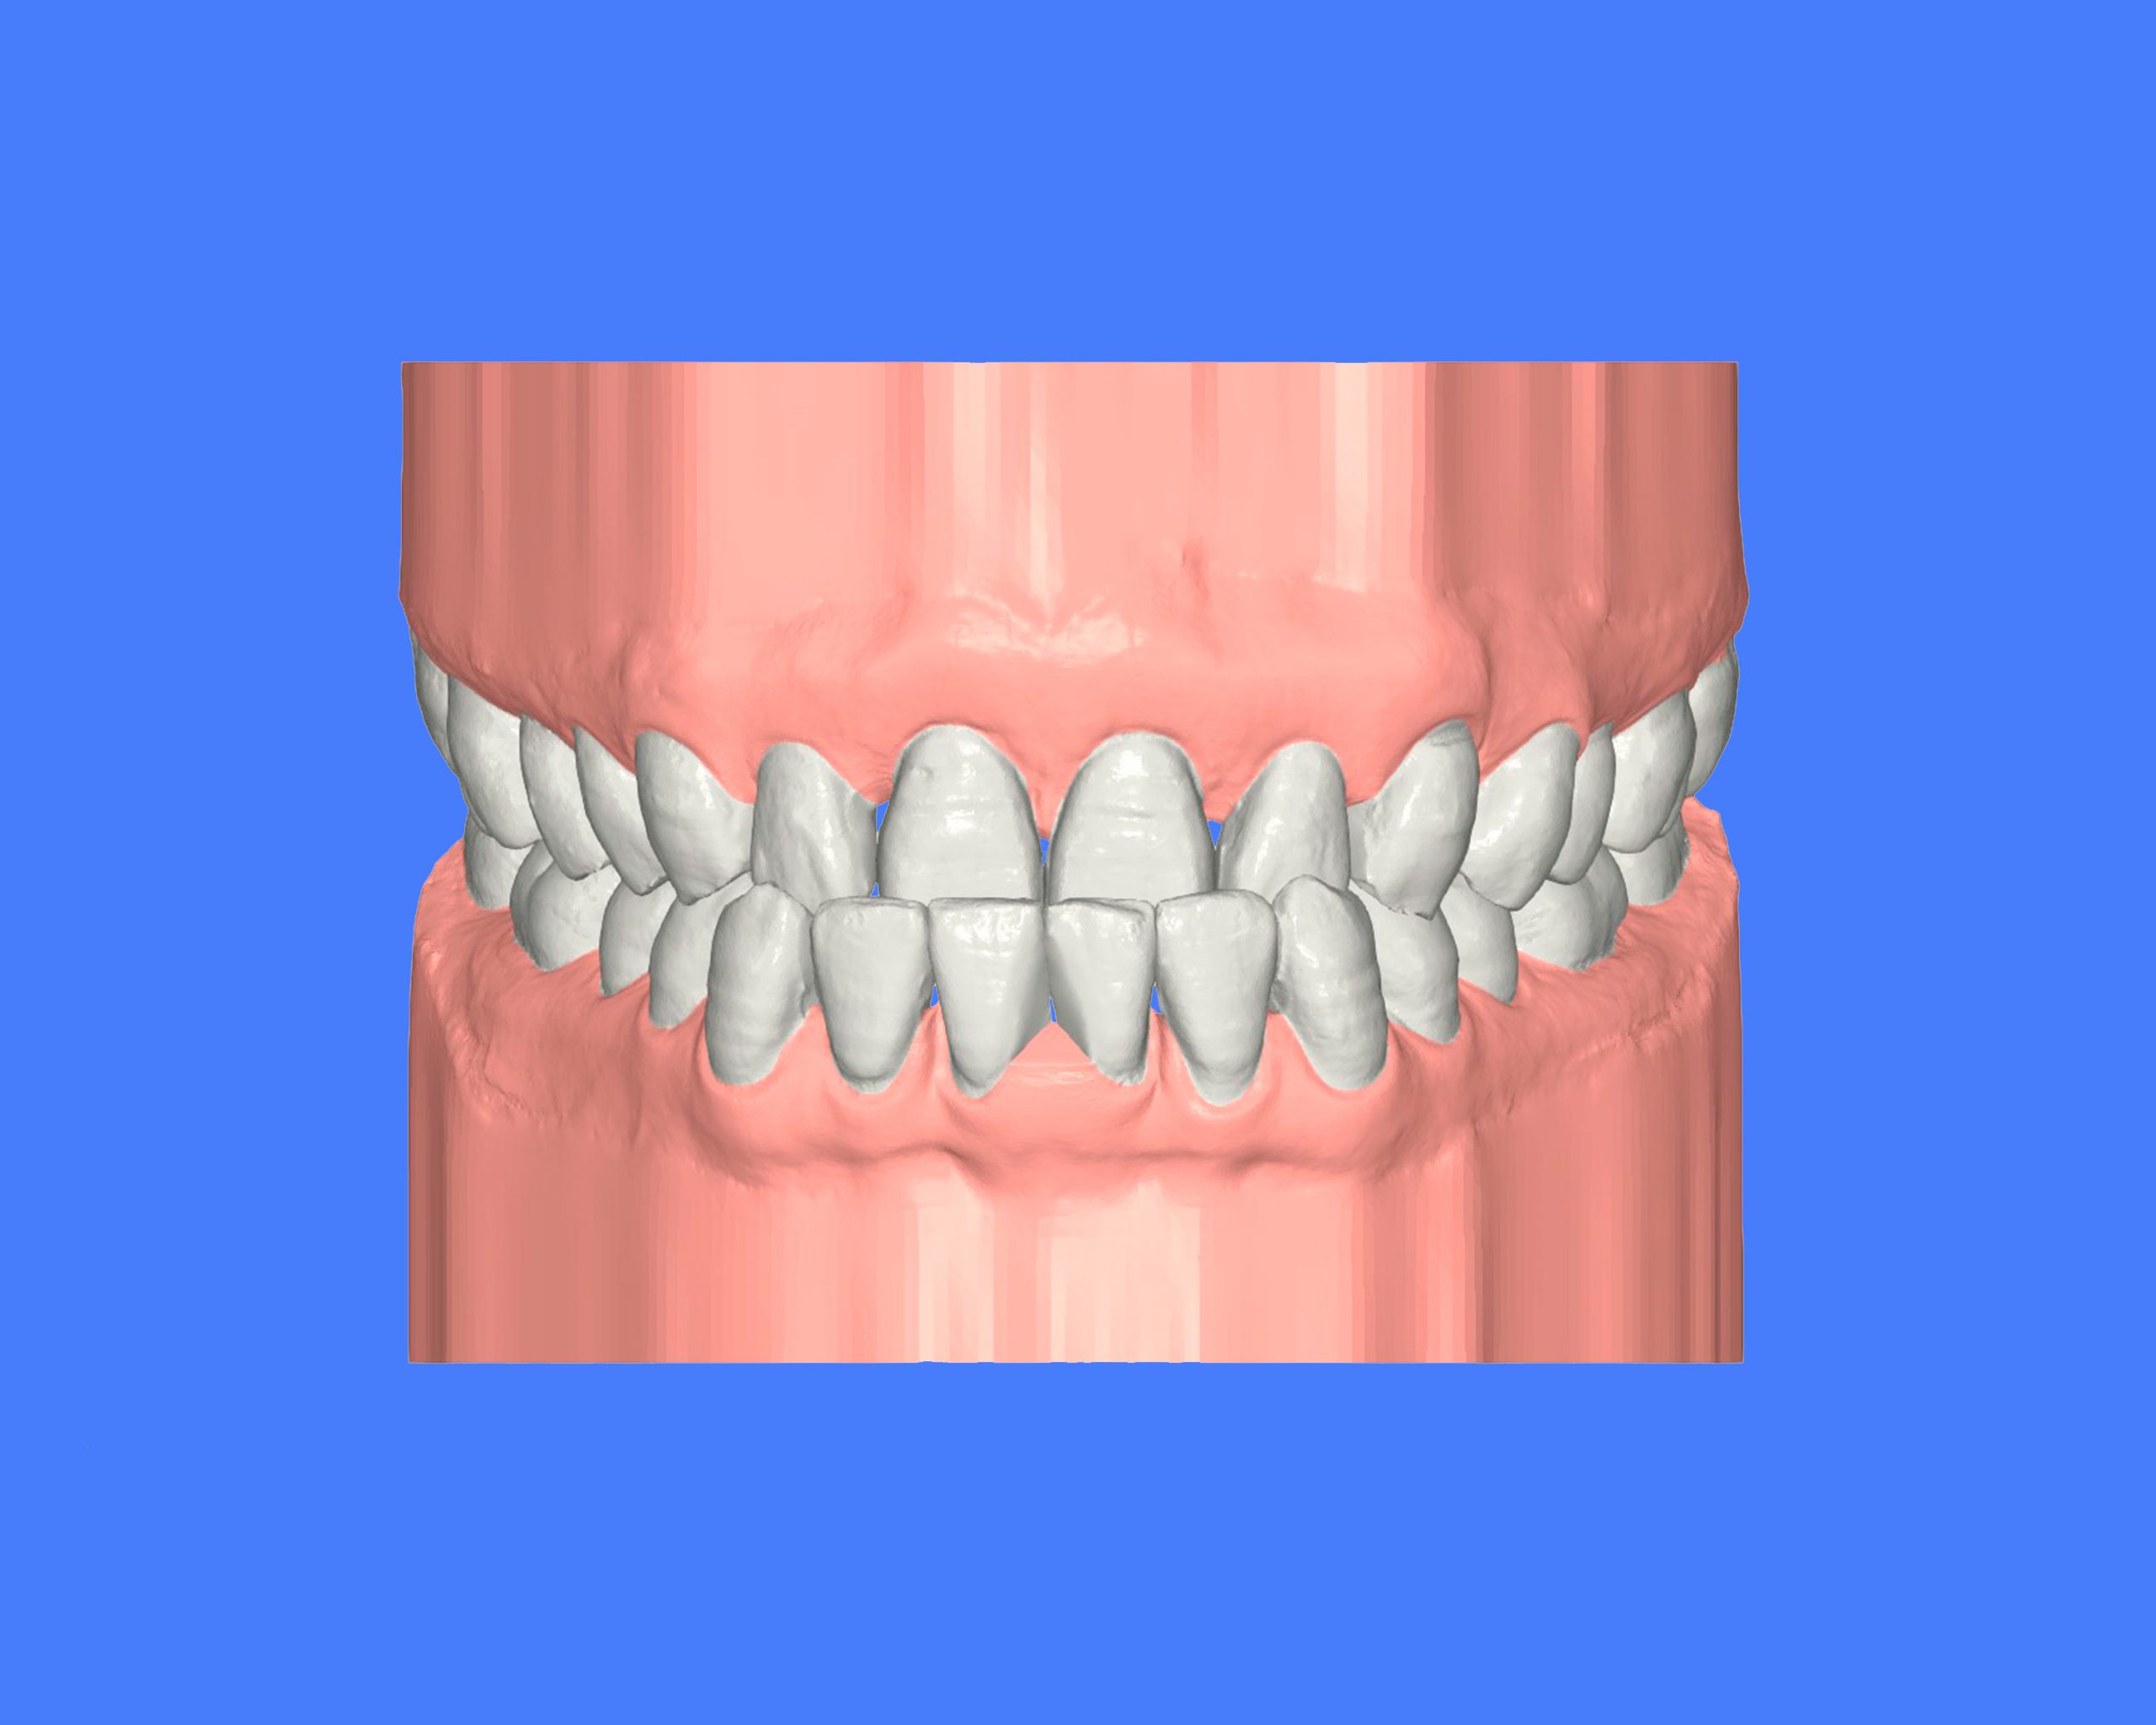

Maloclusión clase II

Se caracteriza por una relación anormal entre los dientes superiores e inferiores, donde los dientes superiores están demasiado adelantados en comparación con los inferiores.

Esto puede generar problemas funcionales, como dificultad para masticar, y también afectar la estética facial.

INTENSIVE

52 Semanas de tratamiento